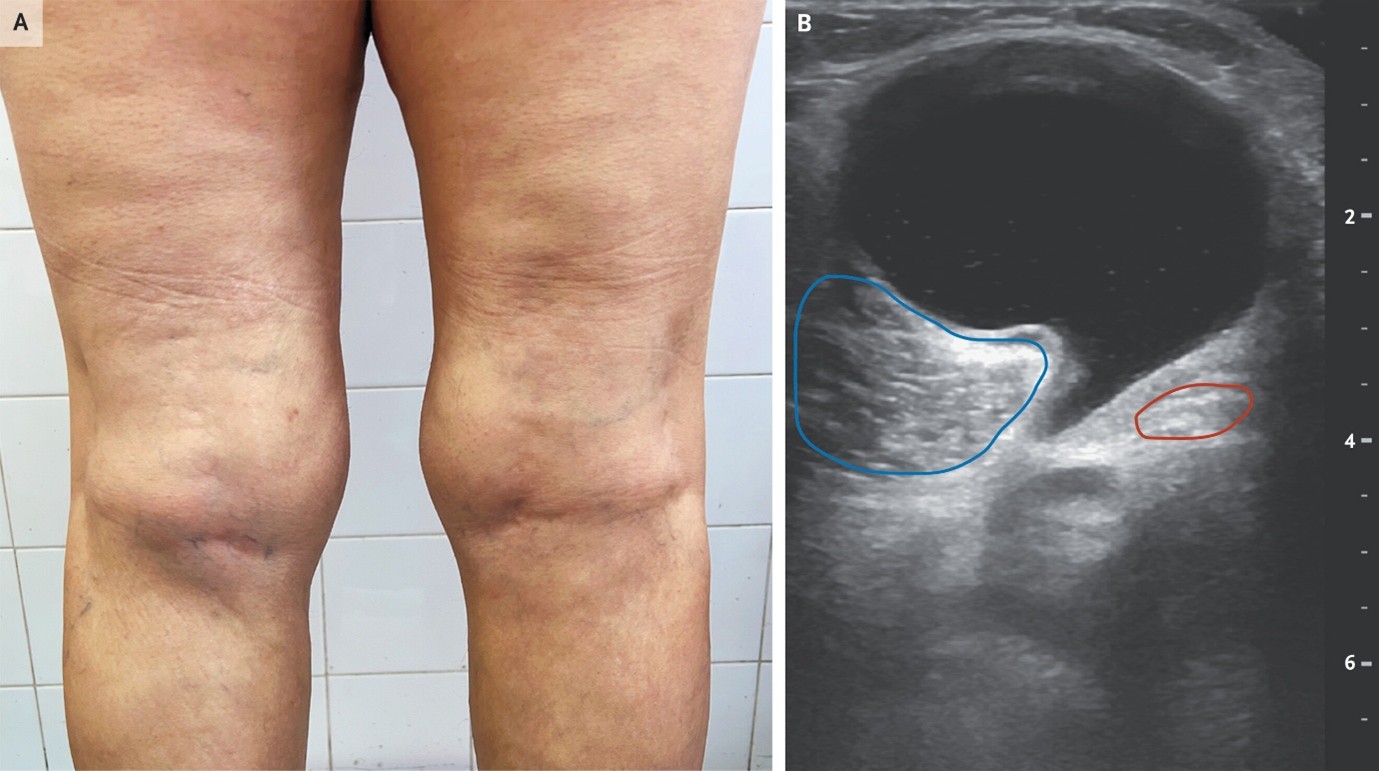

(3). Baker’s Cyst

Burak Karakaya,, Published January 28, 2026,N Engl J Med 2026;394:497,DOI: 10.1056/NEJMicm2513847,VOL. 394 NO. 5

Abstract

A 63-year-old woman with psoriatic arthritis presented with a 9-month history of pain in the left knee. A nontender, palpable mass was present in the left popliteal fossa, which had a “speech bubble” shape on ultrasonography.